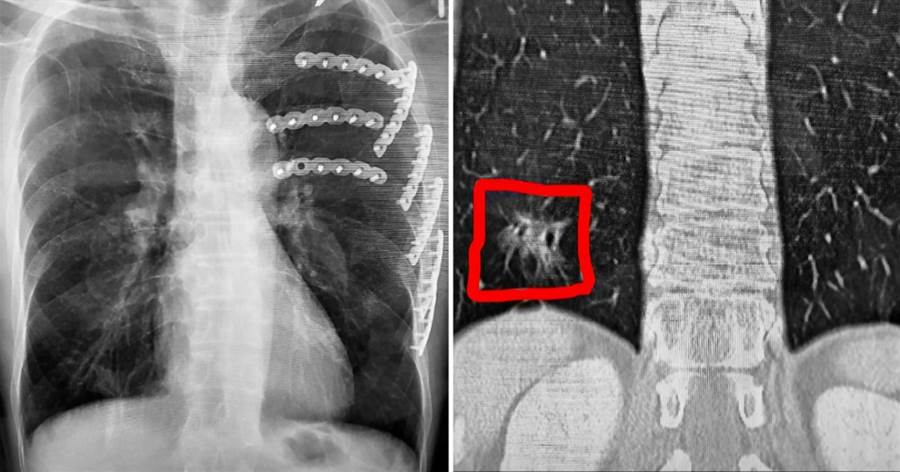

根據《TVBS新聞網》、《自由時報》報導,謝志明主任仔細分析陳先生的斷層掃描影像,赫然發現他的右下肺葉出現疑似癌癥的病灶。

3個月後陳先生回診追蹤肋骨復原狀況,謝醫師發現那處病灶依舊存在,立刻安排他接受第2次「胸腔鏡微創手術」將病灶切除。病理化驗結果證實醫師的判斷沒錯,陳先生確實罹患肺腺癌第1期。謝醫師解釋,一般胸部X光很難偵測到1公分以下的微小病變,許多肺癌病患確診時病情已經相當嚴重。

所幸陳先生這次意外讓他提早發現癌癥,若能在第1期就確診治療,5年存活率可達9成以上。謝醫師也提醒民眾,低劑量電腦斷層是目前唯一經過實證的早期肺癌篩檢利器,國健署目前針對高風險族群提供每2年1次的免費檢查補助,及早發現才能及早治療,別讓健康拉警報才後悔莫及。